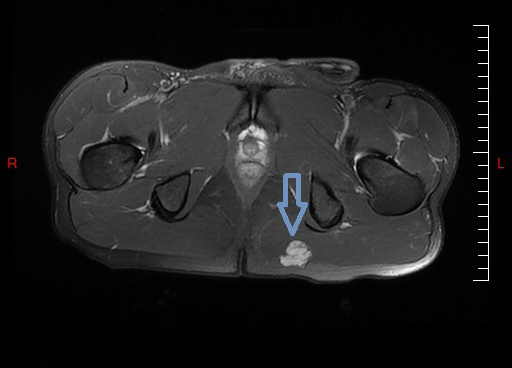

Collection P. Frances IRM d'une myosite ossifiante circonscrite (MOC) post-traumatique développée dans le muscle grand glutéal (ex-grand fessier)